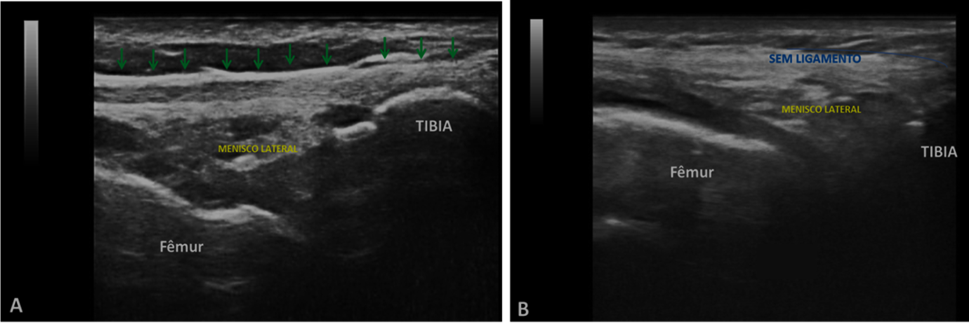

Table 2 shows the side on which the US found the ALL injury. It was considered as a favorable result for the ultrasound evaluation when the ALL injury was found in the same laterality as the patient's ACL injury (ipsilateral); that is, of the 41 patients evaluated, 19 (46.3%) had an ALL injury, seen through ultrasound, on the same side as the ACL injury, and 19 patients (46.3%) did not have an ALL injury (Figure 1). Adding these two groups, there are 38/41 (92.6%) of results favorable to ultrasound, being statistically greater than 50% (p-value <0.001; Z test; unilateral hypothesis).

Figure 1 (A) Longitudinal ultrasound view of a normal anterolateral region, ALL in a right knee, with fibrillary hyperechogenic echotexture of the ALL (arrows); (B) View of longitudinal ultrasound of the anterolateral region in another right knee, without anterolateral ligament.